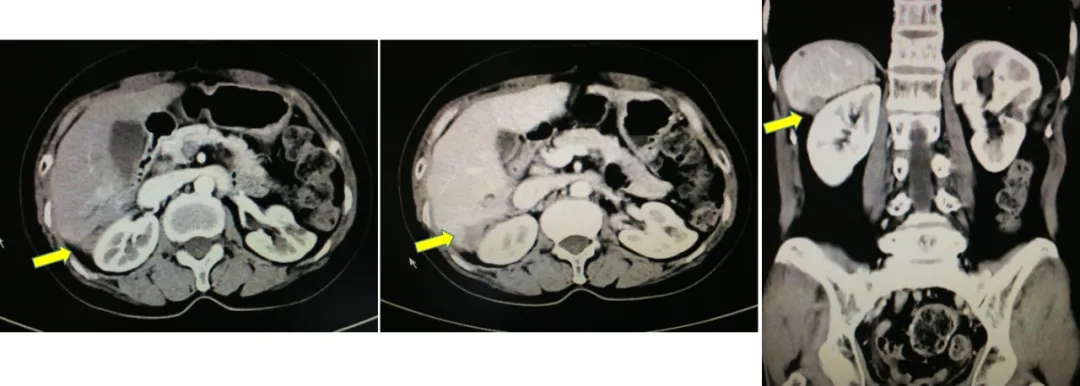

2014.6.11 CT:脾周囊性低密度灶2.4*2.7cm,较2014.2.26增大,腹主动脉旁肿大淋巴结,考虑“卵巢癌复发”。

CT检查结果

2017-10-26当地查CA125水平为46.3U/ml,2017-12-4我院查CA12水平为110.9U/ml,CT显示肝肾间隙及右肝包膜下片状影较前增大,考虑疾病复发。